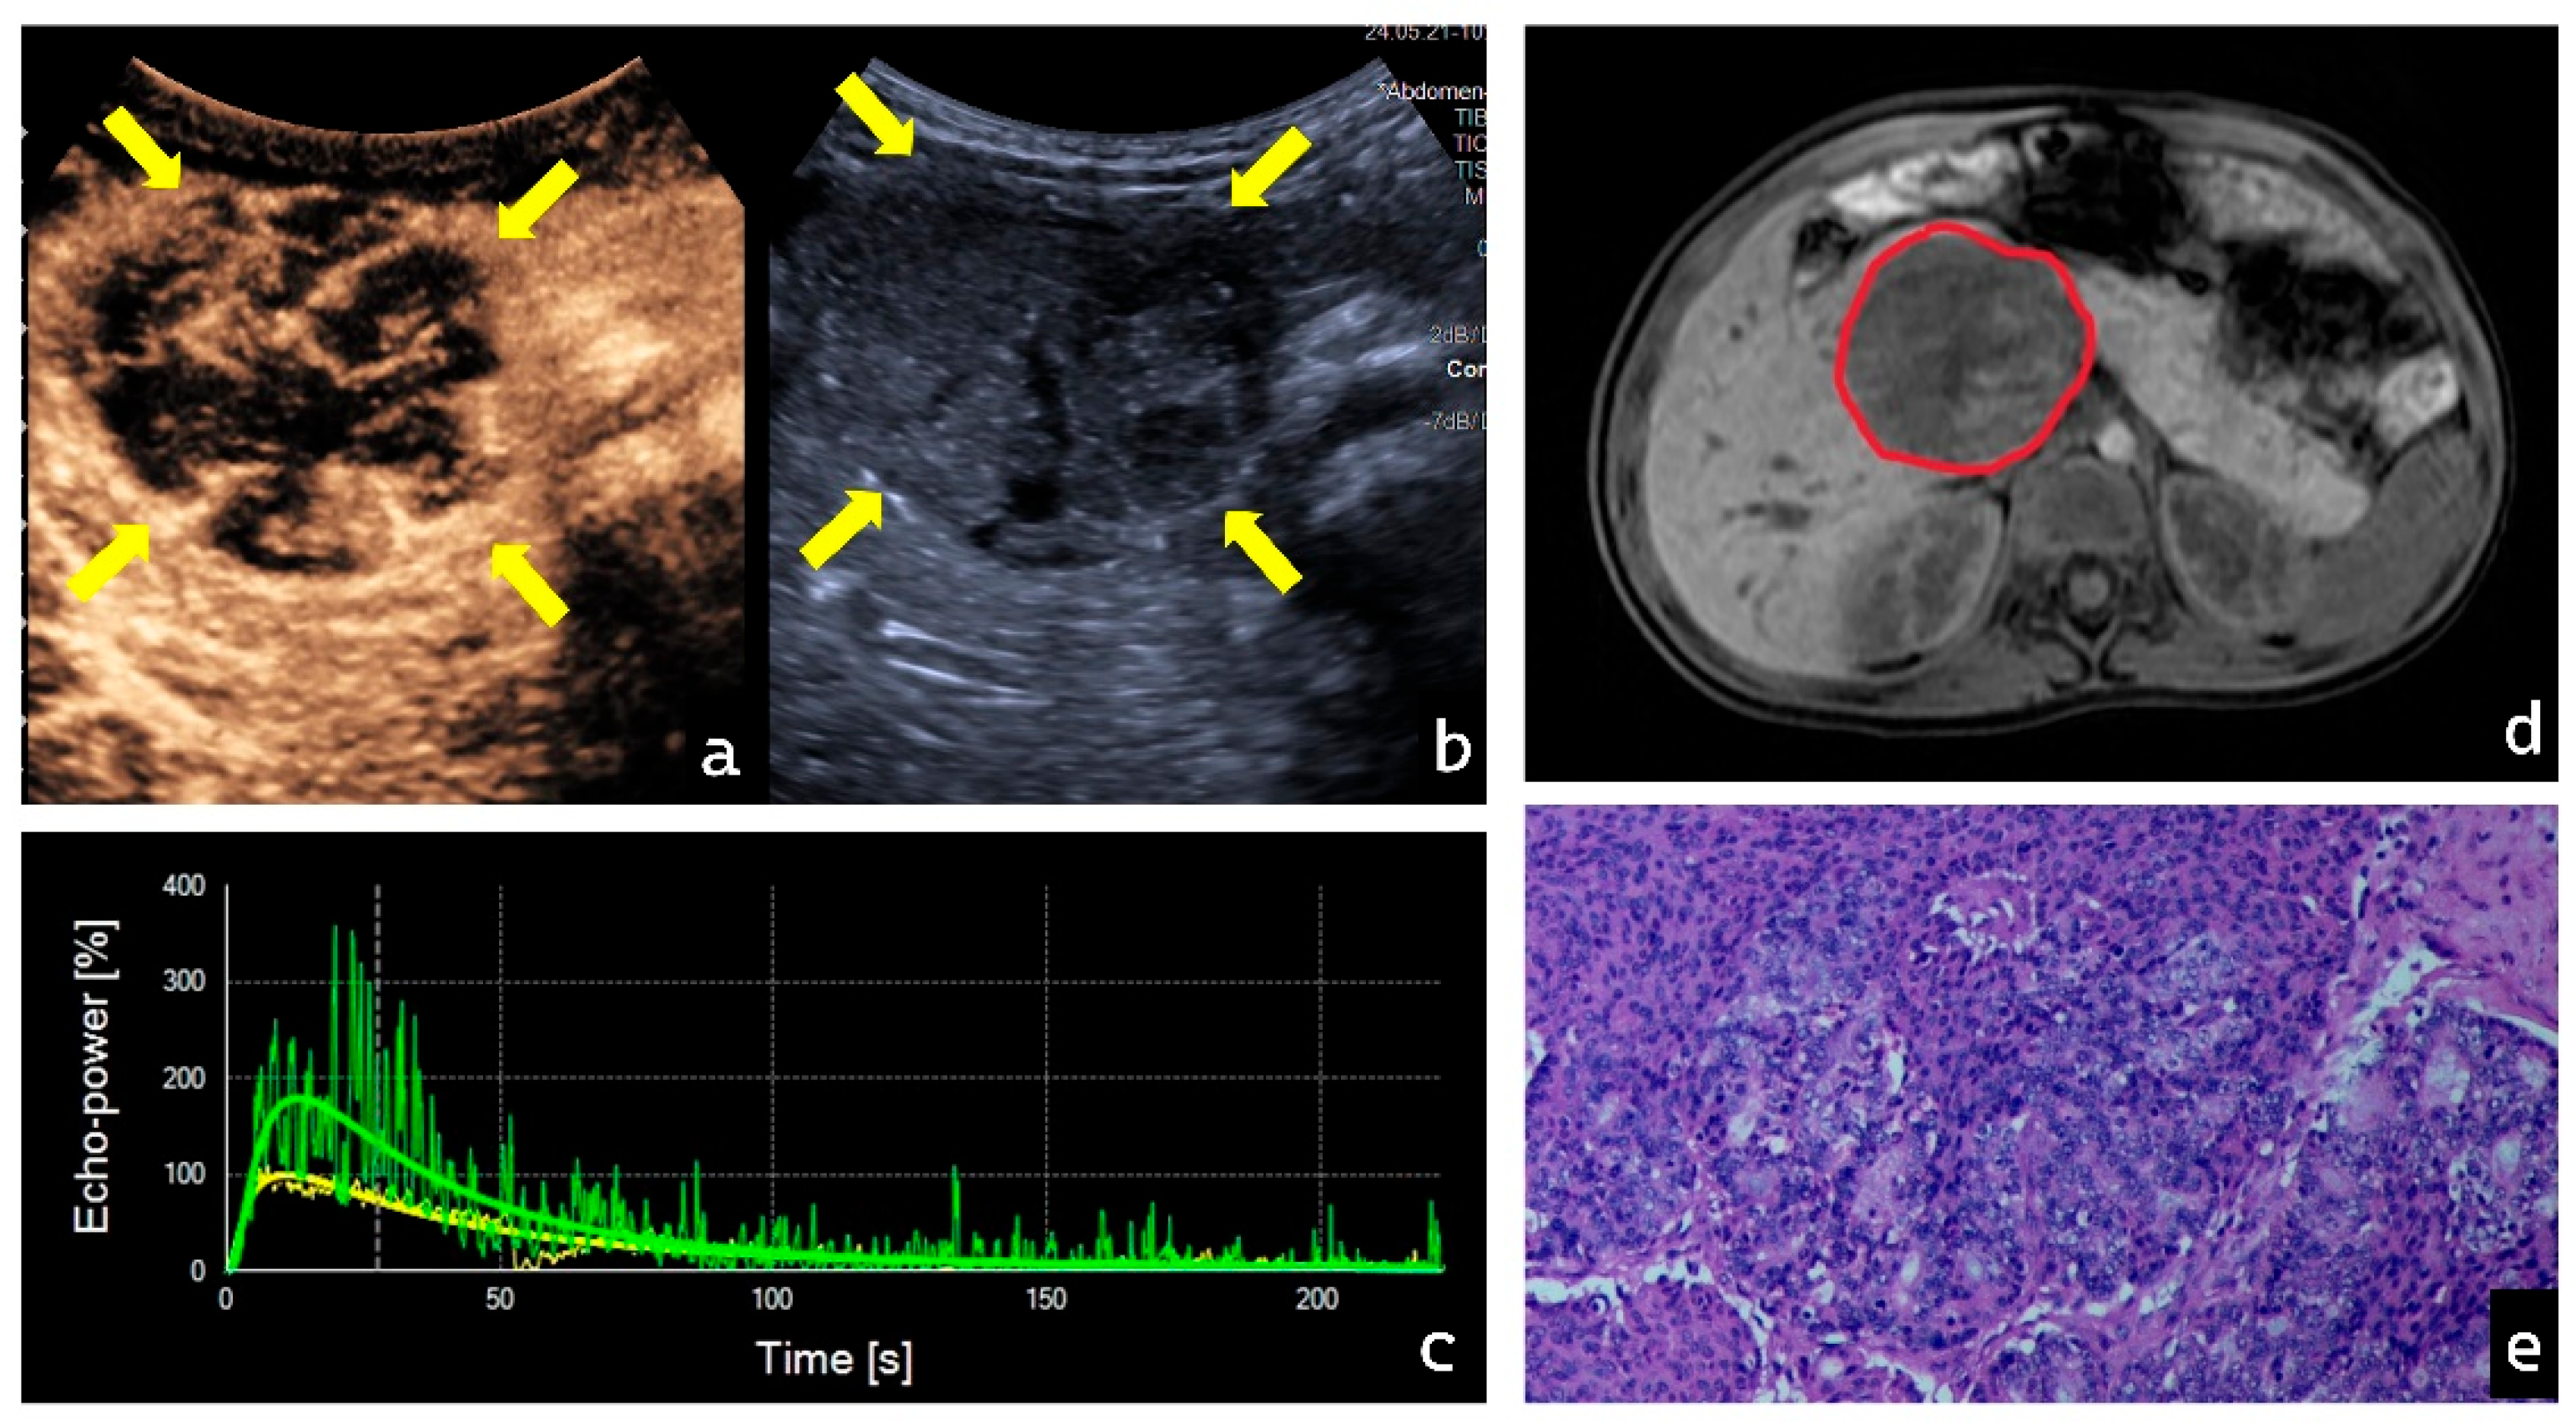

3.4. Visualization of Representative Cases